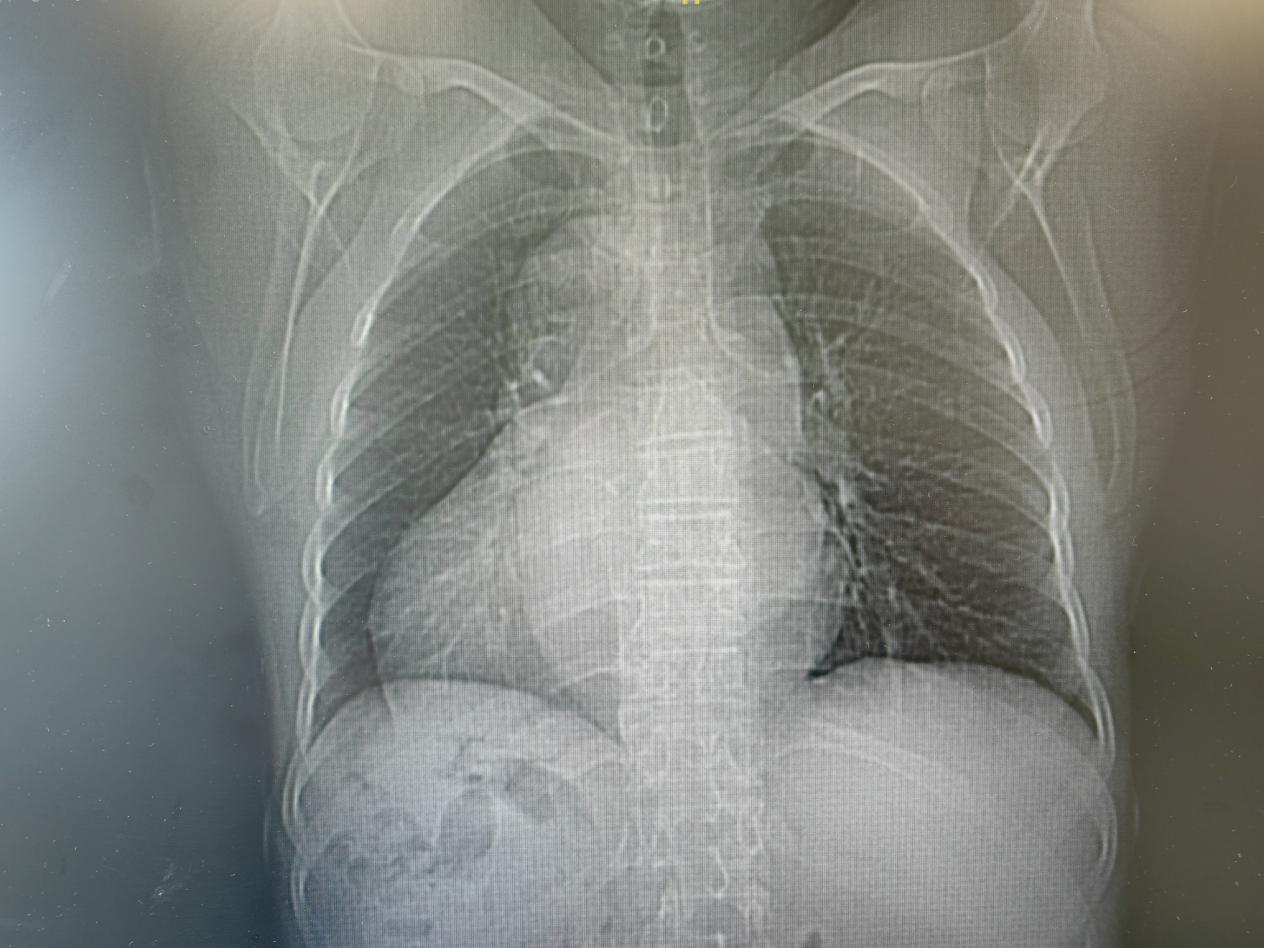

近一个月来,62岁的蔡女士时常觉得胸闷、心悸,特别是活动后喘得厉害,到厦心检查后,被确诊为房颤。而更让人惊讶的是,与正常人心脏位置偏左,心尖部在胸腔左侧相反,蔡女士的心脏却罕见的长在了右胸,就像镜中倒影,一切都与常人相反。

患者的心脏罕见的长在了胸腔右侧